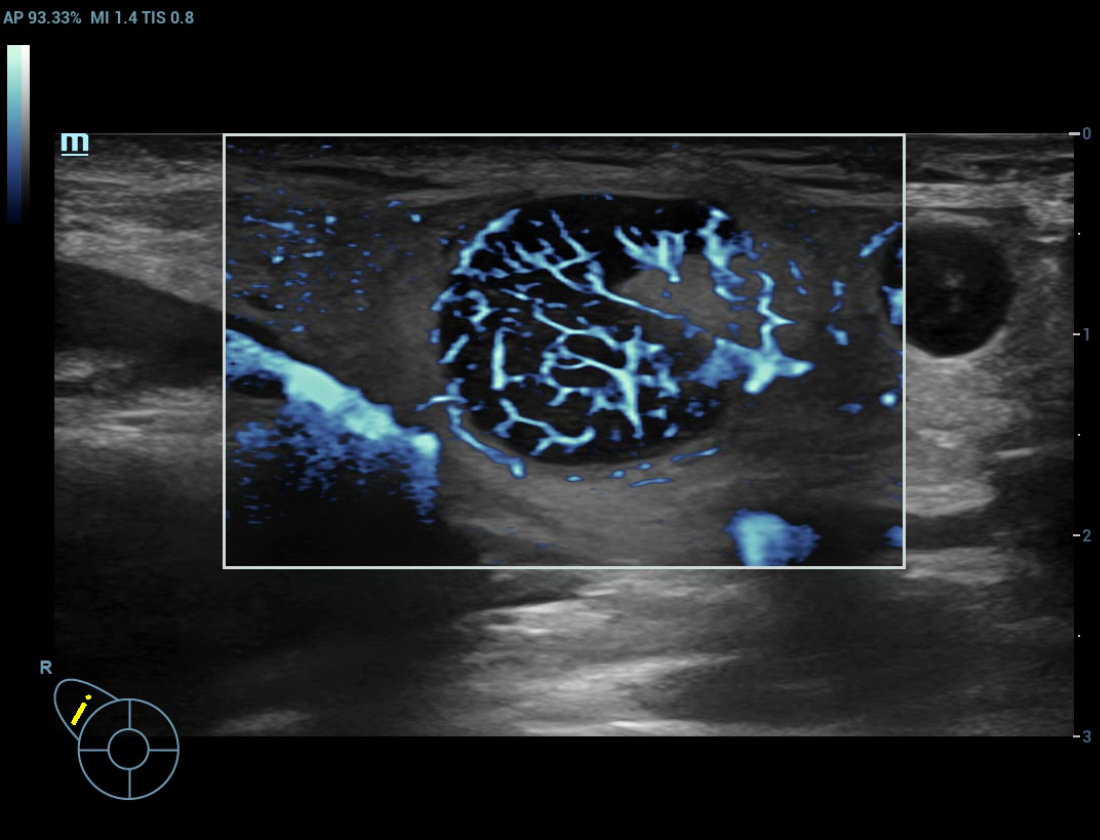

Ultra-Micro-angiografie (UMA)

UMA verbetert het diagnostische vertrouwen door de zichtbaarheid van de bloedstromen uit te breiden tot op het kleinste vaatniveau, met een superieure gevoeligheid en resolutie van de bloedstroom.

pUMA Borstmassa

Borstmassa cUMA

Borstmassa